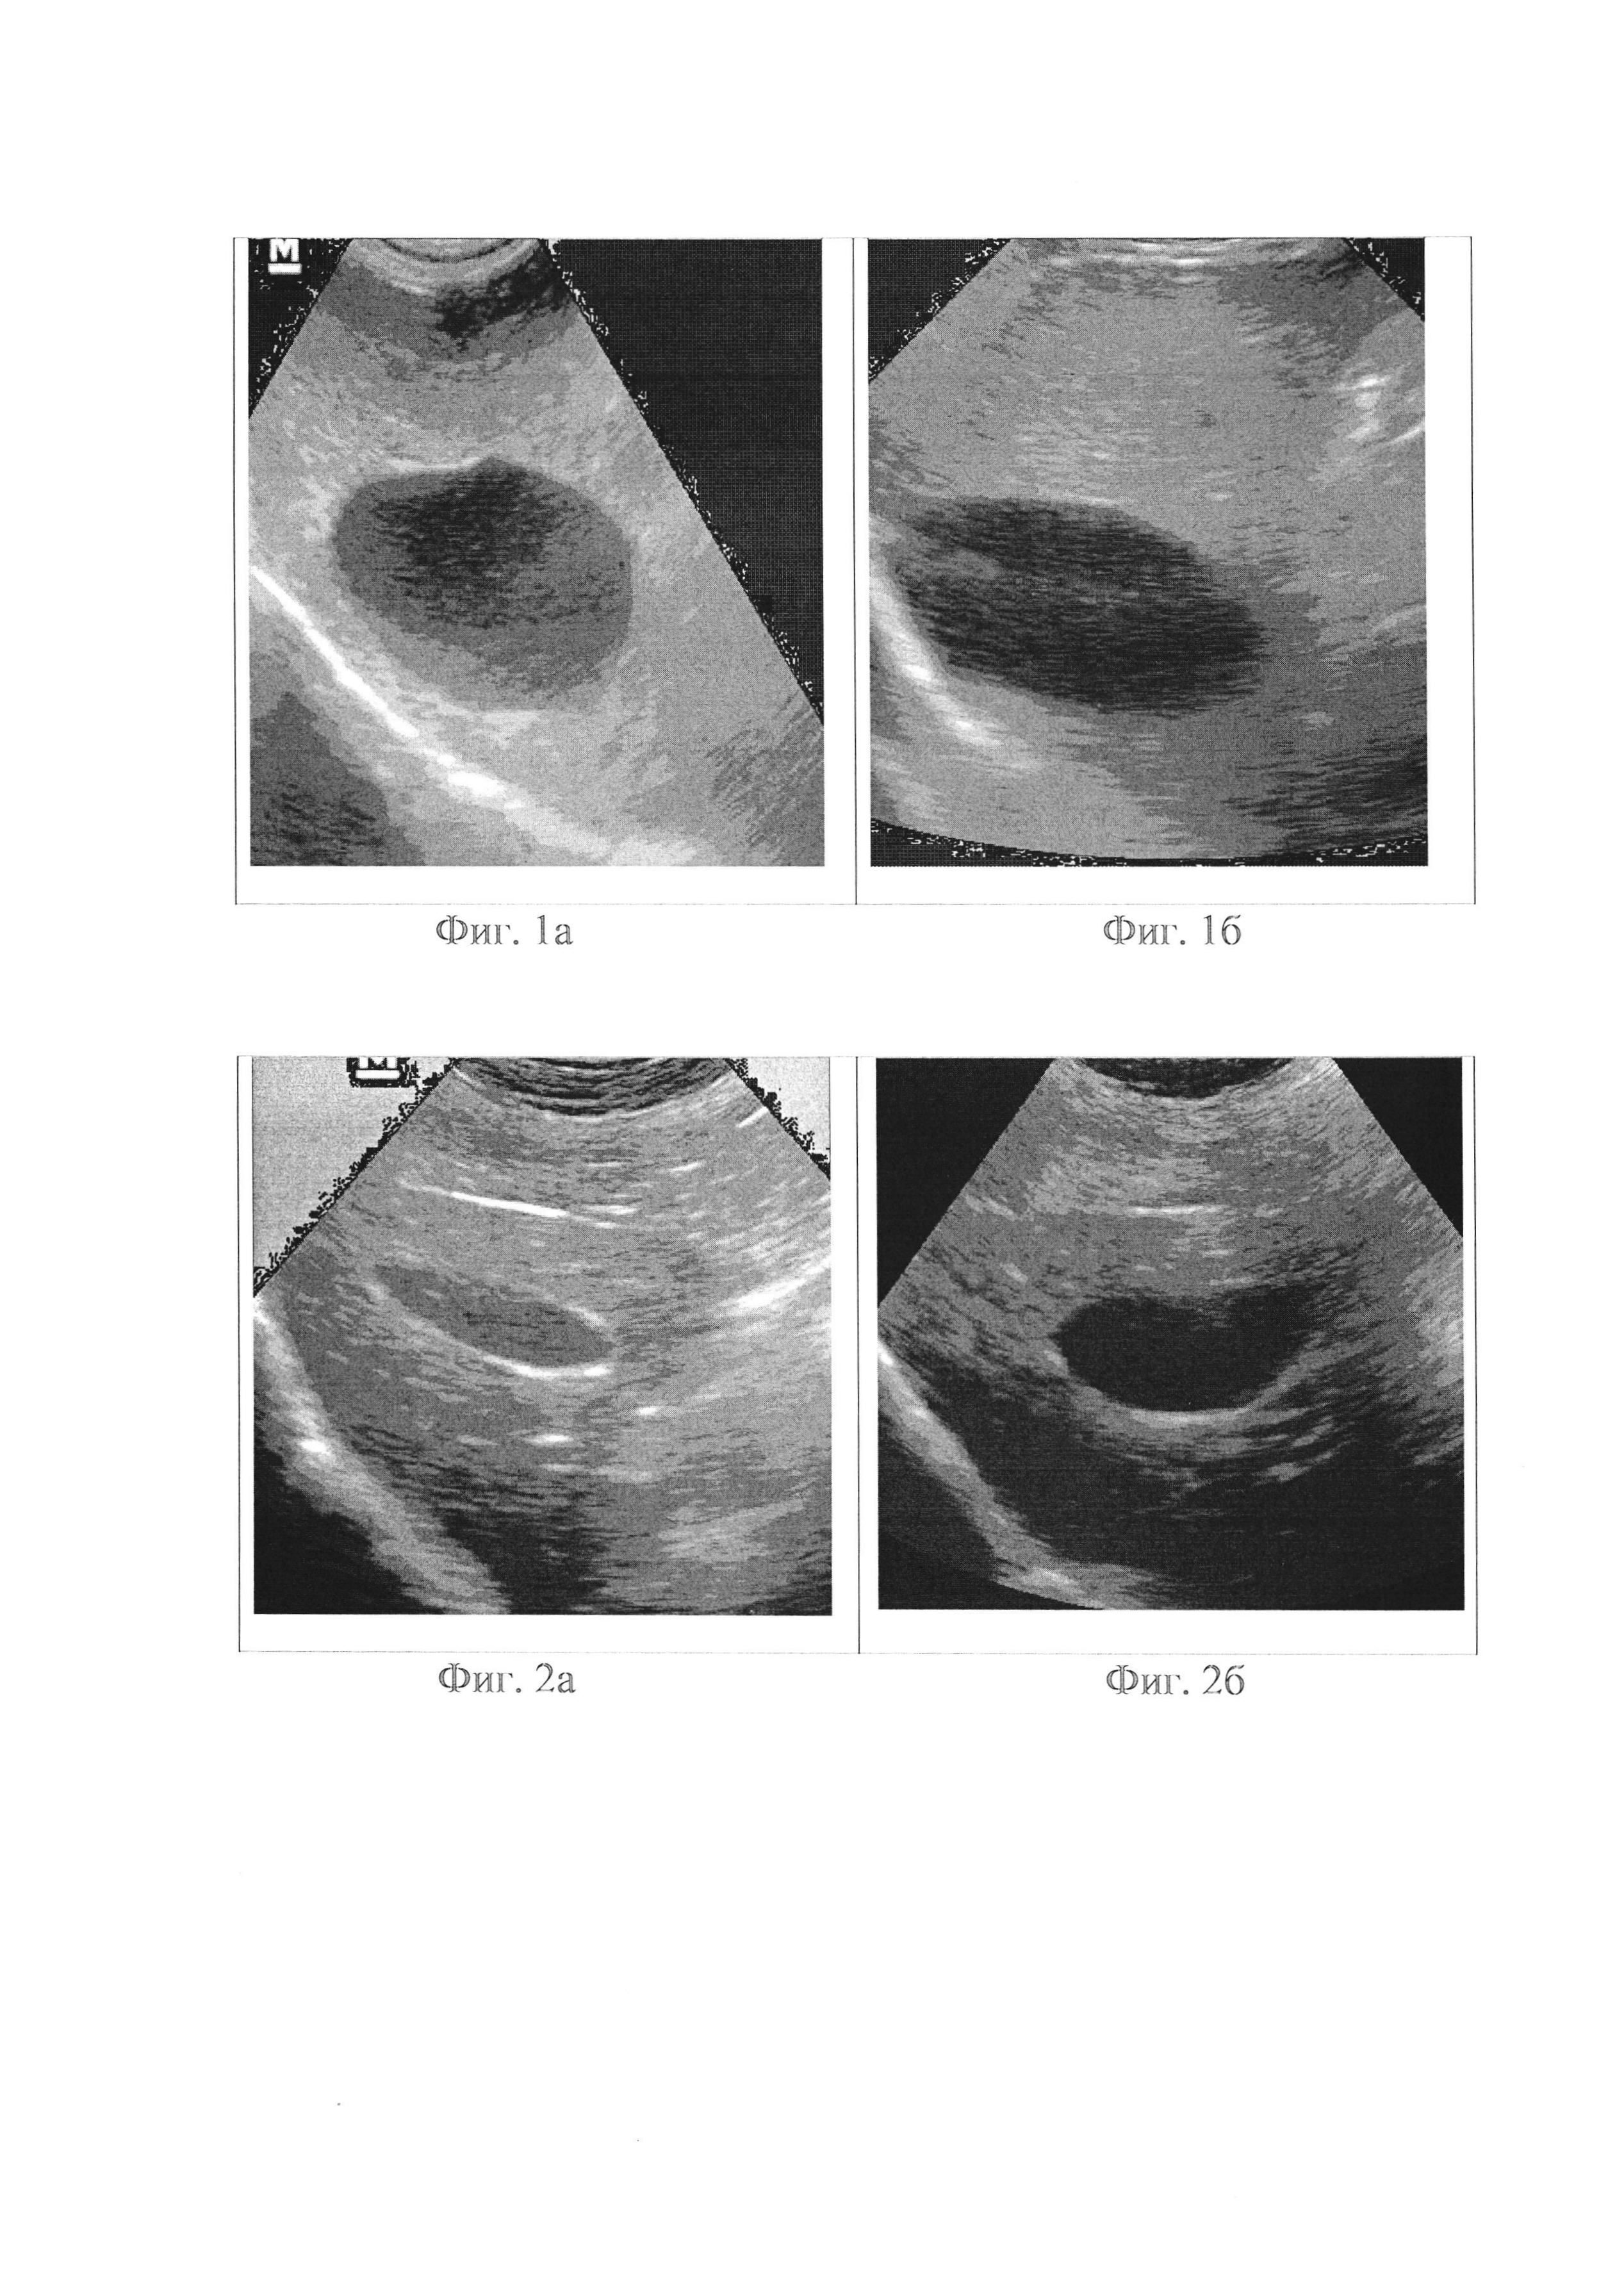

Изобретение относится к гуманитарной и ветеринарной медицине, в частности к средствам для растворения желчных камней и лечения желчнокаменной болезни. Известны средства для растворения желчных камней и лечения желчнокаменной болезни на основе хенодезоксихолевой кислоты: Aylehning, Chebil, Chelobil, Chendal, Chendol, Chenix, Cheno, Chenocol, Chenodex, Chenofalk, Chenossil, Chino, Quenobilan, Quenocol, Soluston, Theramatic) и урсодезоксихолевой (Actigall, Arsacol, Cholit-Ursan, Destolit, Deursil, Litanin, Ursodiol, Ursochol, Ursofalk, Ursolvan, Ursotan (http://www.neboleem.net/ursodezoksiholevaja-kislota.php). В России применялись препараты с действующим веществом хенодезоксихолевая кислота: Хеносан, Хенофальк, Хенохол (http://www.gastroscan.ru/handbook/144/318), а в США - Chenodal (https://health.mail.ru/drug/ursofalk/). Известные средства могут давать побочные реакции (гепатотоксичность, длительные диареи, повышение уровня трансаминаз крови), имеют ряд противопоказаний и высокую стоимость. В результате применения средств на основе урсодезоксихолевой кислоты происходит кальцификация рентгенонегативных (холестериновых) камней. Технический результат от использования предлагаемого средства заключается в возможности растворения желчных камней и лечения желчнокаменной болезни без побочных реакций. Указанный технический результат достигается тем, что используется средство для растворения желчных камней и лечения желчнокаменной болезни, содержащее смесь различных полипренилфосфатов и/или полипренилпирофосфатов растительного происхождения с количеством изопреновых звеньев от 7 до 30 (RU 2427284). Для получения средства в виде таблетированного препарата его адсорбируют на твердом сорбенте, в частности сорбите, лактозе, крахмале. Содержание полипренилпирофосфатов в смеси полипренилфосфатов и полипренилпирофосфатов может составлять 5-20 мас.%, в частности 10 мас.%. Содержание сорбента может составлять 90-99,5 мас.%, в частности 98 мас.%. Средство дополнительно может содержать бета-ситостерин. Содержание бета-ситостерина может составлять 1-10 мас.%, в частности 5 мас.%. Средство применяют в виде: - 0,4% раствора в комплексном водном растворителе полипренилфосфата натрия, полученного путем фосфорилирования полипренолов хвойных растений (число изопреновых звеньев от 12 до 18) в присутствии едкого натра и ацетата натрия (Пример 1, Фоспренил: http://www.vidal.ru/veterinar/phosprenyl-27881). В таком виде средство применяют по 2 мл перорально, 0,5% раствора в комплексном водном растворителе полипренилфосфата натрия, полученного путем фосфорилирования полипренолов из листьев шелковицы (число изопреновых звеньев от 8 до 16) в присутствии едкого натра и ацетата натрия (Пример 1, Гамапрен: http://www.vidal.ru/veterinar/gamapren-27879). В таком виде средство применяют по 2 мл перорально, 2 раза в день в течение 2-6 месяцев. - таблетированного препарата, содержащего в качестве действующих веществ 8 мг натрия полипренилфосфата из хвойных растений и 10 мг бета-ситостерина, а в качестве вспомогательных веществ: стеарат магния - 2,5 мг и сорбит - 229,5 мг, на 1 таблетку массой 250 мг (Примеры 1-4, Преностерол: RU 2542420). В таком виде средство применяют внутрь по 0,5-2 таблетки два раза в день (в зависимости от массы тела) и сочетают с обычным приемом пищи. Длительность курсового применения зависит от диаметра камней, их количества, функционального состояния желчного пузыря и может колебаться от 2 до 6 месяцев. Способ получения полипренилфосфатов описан в RU 2471804. Ниже приведены примеры лечения желчнокаменной болезни с использованием предлагаемого средства. Пример 1. Исследования были произведены на 20-и собаках - 10-и самцах и 10-и самках, в возрасте 5-12 лет, взятых из приюта. Прижизненный диагноз у отобранных животных, подтвержденный клиническими, биохимическими и УЗИ исследованиями: холангит, холестаз, желчнокаменная болезнь. Периодически у собак брали сыворотку крови на биохимический анализ. Указанное средство собаки получали вместе с основной пищей в течение 3-6 месяцев согласно схеме, описанной выше. Результаты исследования крови отражены в таблице. При поступлении у животных в крови отмечались повышение уровня билирубина, щелочной фосфатазы и γ-глутамилтранспептидазы, после завершения курса приема средства все эти показатели пришли в норму. Особенно сильный эффект наблюдается после применения таблетированной формы (Преностерола). Пример 2. Исследования были произведены на 10-и собаках - 5-и самцах и 5-и самках, в возрасте 5-12 лет, взятых из приюта. Прижизненный диагноз у отобранных животных, подтвержденный клиническими, биохимическими и УЗИ исследованиями: холангит, холестаз, желчнокаменная болезнь. Периодически у собак брали сыворотку крови на биохимический анализ. Указанное средство собаки получали вместе с основной пищей в течение 3-6 месяцев согласно Наставлению по 1 таблетке 2 раза в день. Результаты исследования крови отражены в таблице. При поступлении у животных в крови отмечались повышение уровня билирубина, щелочной фосфатазы и γ-глутамилтранспептидазы, после завершения курса приема средства все эти показатели пришли в норму. Пример 3. Исследования проведены на 6-и собаках - 3-х самцах и 3-х самках, в возрасте 4-10 лет, взятых из приюта. Прижизненный диагноз у отобранных животных, подтвержденный клиническими, биохимическими и УЗИ исследованиями: холангит, холестаз, желчнокаменная болезнь. Периодически собакам проводили УЗИ. Указанное средство собаки получали вместе с основной пищей в течение 3-6 месяцев согласно Наставлению по 1 таблетке 2 раза в день. На УЗИ при поступлении у большинства пациентов стенка желчного пузыря неравномерно утолщена, в органе визуализируется значительное количество рыхлого, подвижного осадка, выявляются гиперэхогенные образования, в ряде случаев - конкременты высокой эхогенности. По окончании приема средства холестазные явления уменьшаются, становится тоньше стеночка желчного пузыря, снижаются до полного исчезновения гиперэхогенные образования и конкременты, рыхлый подвижный осадок исчезает. Ультразвуковые исследования собак. Ниже приведены ультрасонограммы 6-и типичных случаев патологии желчного пузыря у собак (холангиты, холестазы, желчнокаменная болезнь) до и после лечения. Животное 1. До лечения: желчный пузырь округлый, стенка тонкая. В органе на 1/3 объема визуализируется рыхлый, подвижный осадок. Паренхима печени повышенной эхогенности (фиг. 1а). Через два месяца лечения: желчный пузырь округлый, стенка тонкая. В органе на 1/10 объема визуализируется рыхлый, подвижный осадок. Паренхима печени по плотности приблизилась к физиологической норме (фиг. 1б). Животное 2. До лечения: желчный пузырь продолговатый, стенка неравномерно утолщена, в органе визуализируется незначительное количество рыхлого подвижного осадка (фиг. 2а). Через два месяца лечения: стенка тонкая, осадка в желчном пузыре нет (фиг. 2б). Животное 3. До лечения: желчный пузырь продолговатой формы, в органе на одну треть визуализируется рыхлый подвижный осадок, не отбрасывающий акустической тени (фиг. 3а). Через два месяца лечения: желчный пузырь продолговатой формы, осадок не визуализируется (фиг. 3б). Животное 4. До лечения: желчный пузырь овальный, в органе визуализируются конкременты высокой эхогенности и рыхлый подвижный осадок, стенка органа рыхлая, неравномерно утолщена (фиг. 4а). Через два месяца лечения: стенка утолщена, осадка и конкрементов нет (фиг. 4б). Животное 5. До лечения: орган округлой формы, стенка тонкая, в органе визуализируется незначительное количество рыхлого подвижного осадка (фиг. 5а). Через два месяца лечения: орган округлой формы, стенка тонкая, в просвете пузыря визуализируется крайне незначительное количество сгущенной желчи (фиг. 5б). Животное 6. До лечения: орган продолговатой формы, визуализируется сгущенная желчь и рыхлый подвижный осадок (фиг. 6а). Через два месяца лечения: визуализируется явное снижение количества сгущенной желчи (фиг. 6б). На представленных ультрасонограммах отчетливо видно, что после лечения средством гиперэхогенные образования в желчном пузыре собак (сгущенная желчь, мелкие конкременты) значительно уменьшаются количественно (вплоть до полного исчезновения) при улучшении общеклинических показателей. Пример 4. Кошка породы корниш рекс, возраст 3 года. До лечения: структура печени неоднородная, крупнозернистая. Эхогенность паренхимы печени L=67-70 (норма L=65-68). Края печени ровные, закругленные. Желчный пузырь - переполнен, продолговатый с тонкими стенками и неоднородным, анэхогенным содержимым. Желчные ходы расширены, переполнены (фиг. 7а). После лечения: структура печени неоднородная, крупнозернистая. Эхогенность паренхимы печени L=65-68 (норма L=65-68). Края печени ровные, закругленные. Желчный пузырь - округлый с тонкими стенками и однородным, анэхогенным содержимым. Желчные ходы без ярко выраженных ультрасонографических изменений (фиг. 7б). Выводы: после приема средства эхогенность паренхимы печени пришла в норму, исчез осадок в желчном пузыре и застой желчи в желчных ходах и желчном пузыре. Применяемое средство для растворения желчных камней высокоэффективно у различных видов млекопитающих, имеет натуральное происхождение, экологически чисто, простое в применении, хорошо переносится больными и не вызывает побочных реакций при длительном использовании, так как является пищевым продуктом животного происхождения, а также экономична вследствие использования недорогих компонентов.